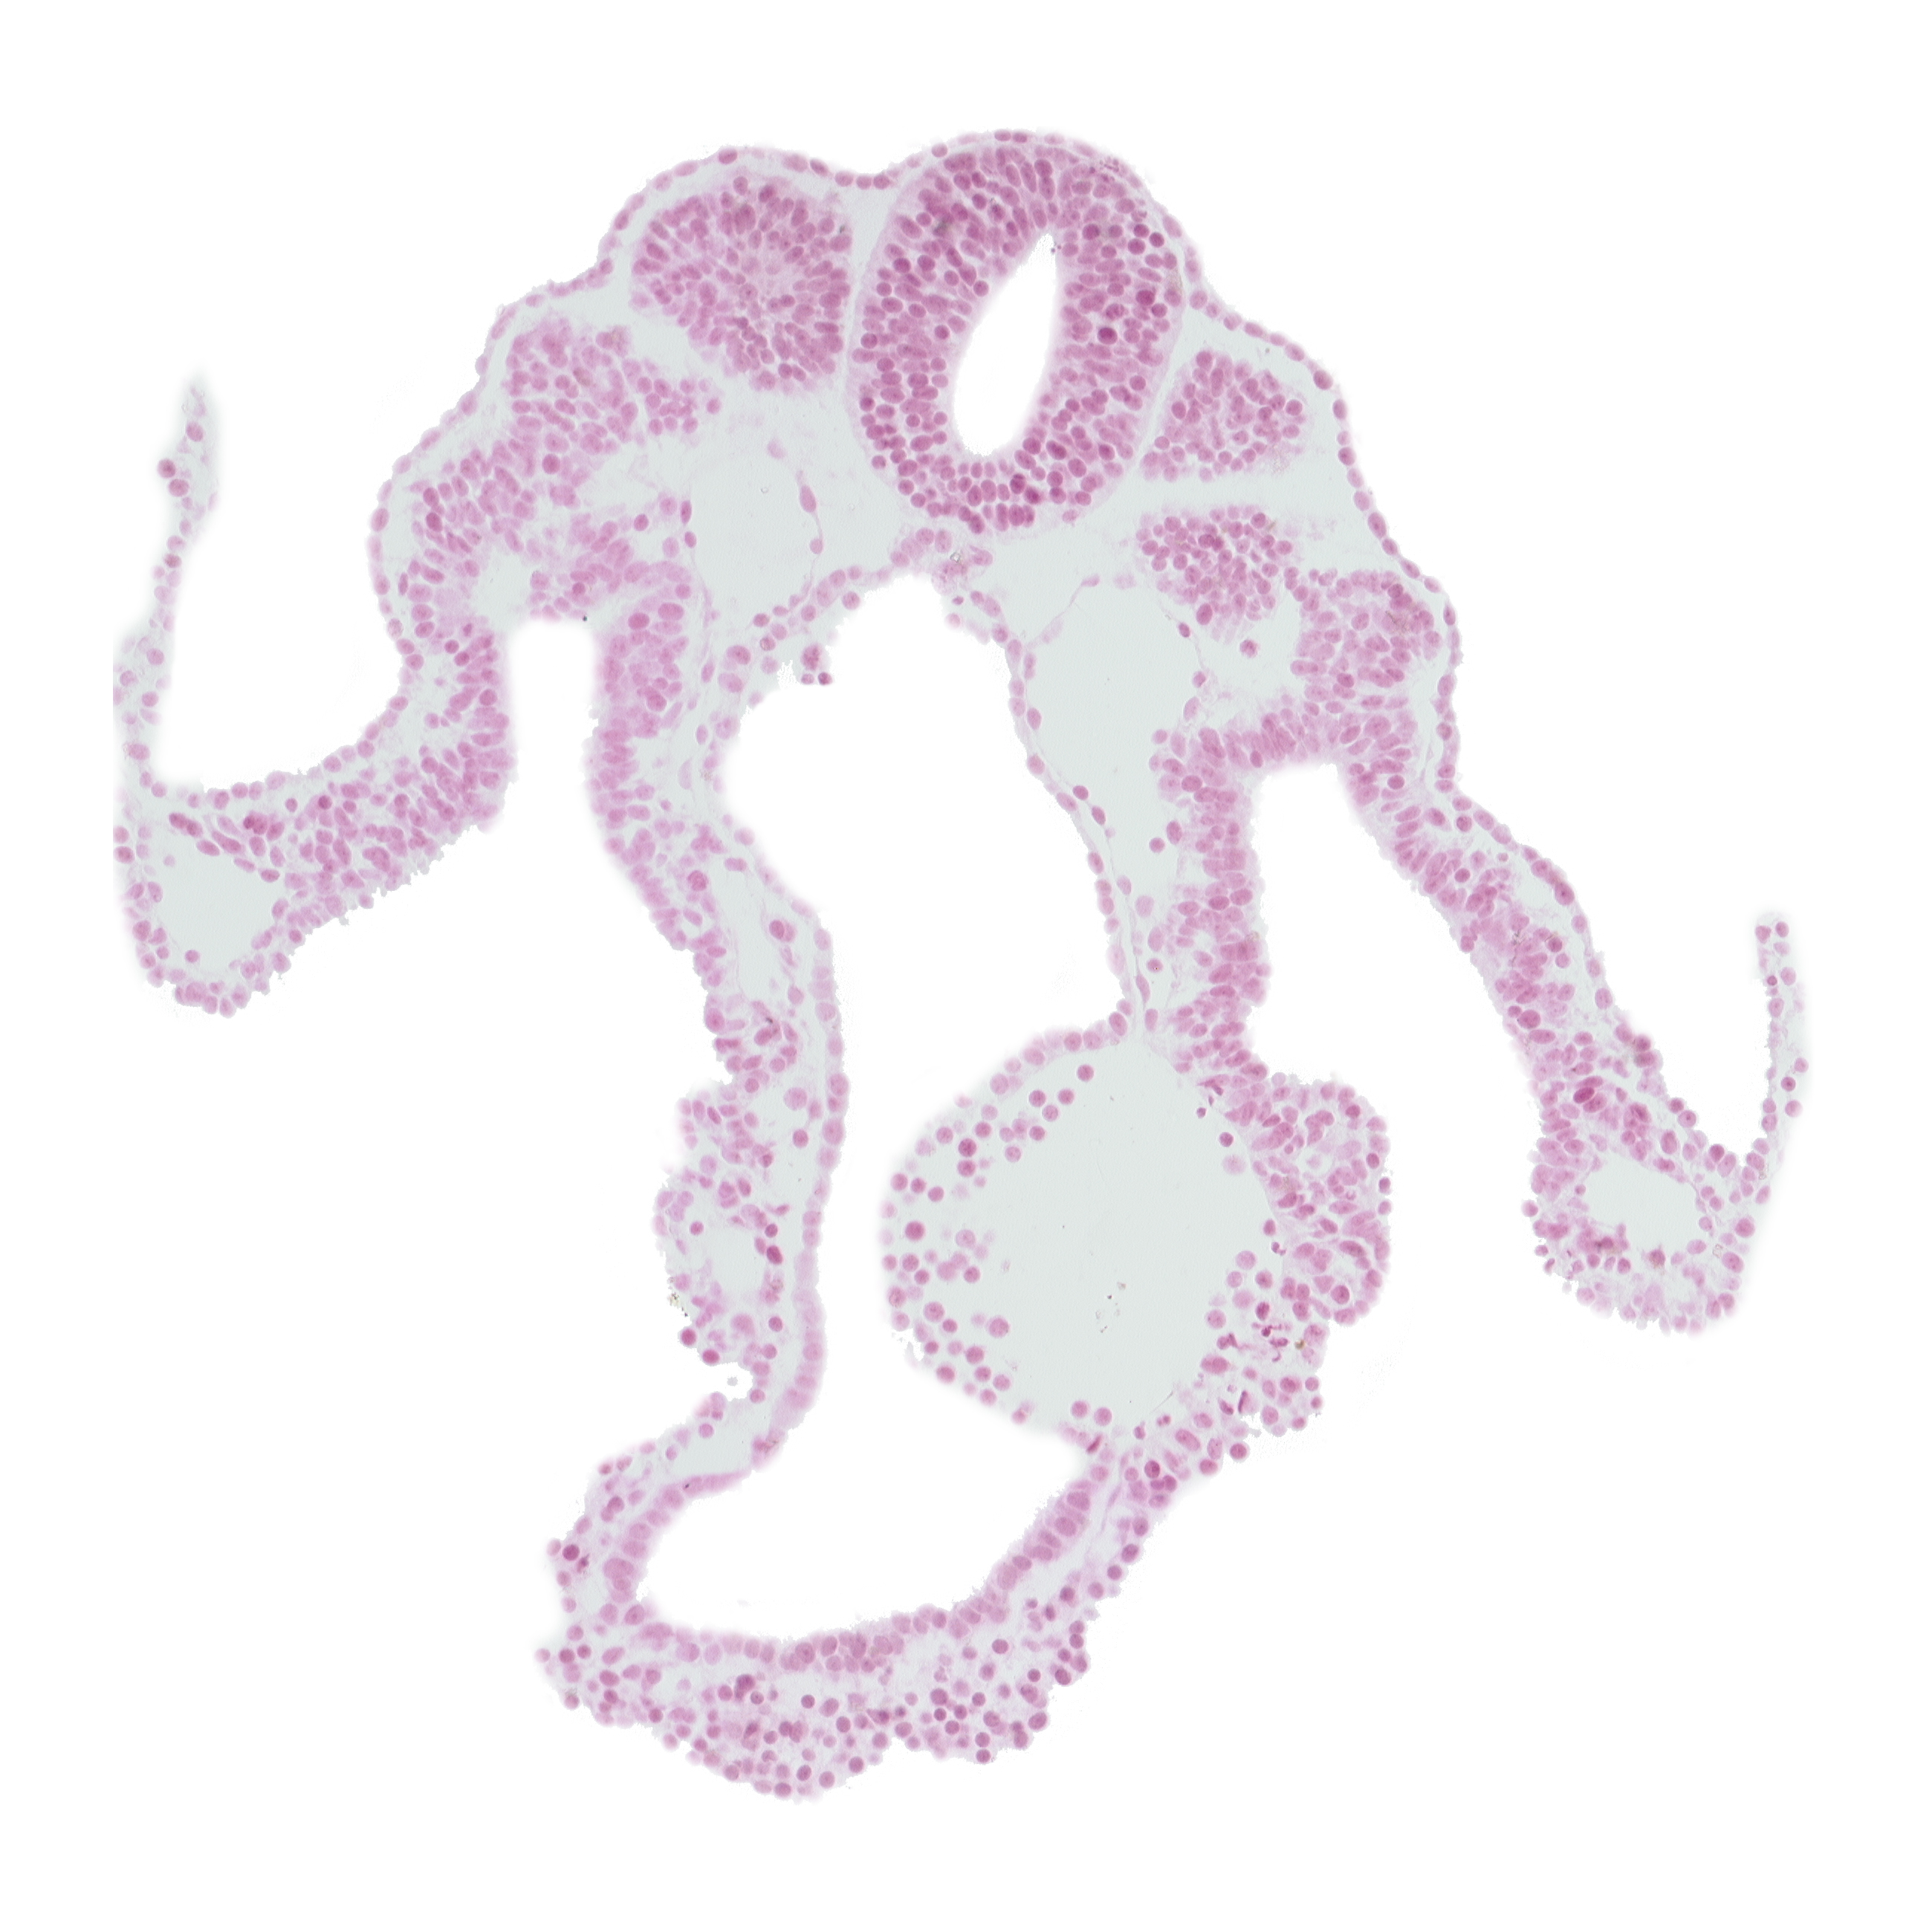

Carnegie Embryo #6344 | Location: 05-02-10

Keywords: caudal part of dermatomyotome 9 (C-5), cephalic part of somite 10 (C-6), lateral body fold, left umbilical vein, midgut, neural tube, peritoneal cavity, right umbilical vein

Source: The Virtual Human Embryo.